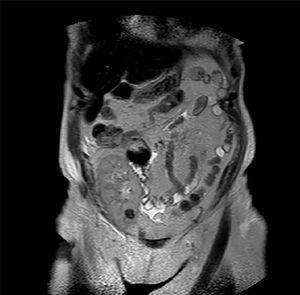

Caso 1. Varón de 56 años que inicia hemodiálisis en 1990 por nefropatía hipertensiva y en 1992 se le somete a un trasplante renal de donante cadáver que evolucionó sin complicaciones. En 2006, estando asintomático y por un deterioro de la función renal, se detecta por ecografía una masa en polo superior del injerto de 5 cm de diámetro máximo. Se procedió a una biopsia percutánea de la masa que confirmó la presencia de carcinoma de células renales. Se llevó a cabo un estudio de extensión con TAC (figura 1) y resonancia magnética nuclear (RMN), que no mostró extensión locorregional, y se procedió a transplantectomía extracapsular con linfadenectomía. El resultado en la anatomía patológica definitiva fue de carcinoma de células claras variante sarcomatoide de 5 cm infiltrando la cápsula del riñón y tejidos circundantes sin infiltración de vena ni de ganglios resecados (pT3aN0). Tras 6,5 años de seguimiento, el paciente está libre de enfermedad. En el estudio genético con micro-arrays de DNA se evidenció el origen tumoral de las células del propio paciente. Se descartó la presencia de neoplasia en los riñones nativos, y por tanto la hipótesis de metástasis procedente de estos.

Figura 1. Carcinoma de células renales variante sarcomatoide